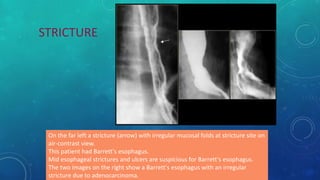

On the far left a stricture (arrow) with irregular mucosal folds at stricture site on

air-contrast view.

This patient had Barrett's esophagus.

Mid esophageal strictures and ulcers are suspicious for Barrett's esophagus.

The two images on the right show a Barrett's esophagus with an irregular

stricture due to adenocarcinoma.

STRICTURE